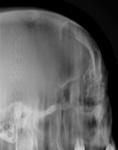

Фрагменты рентгенограмм.

Признаки прерывания кортикального слоя?